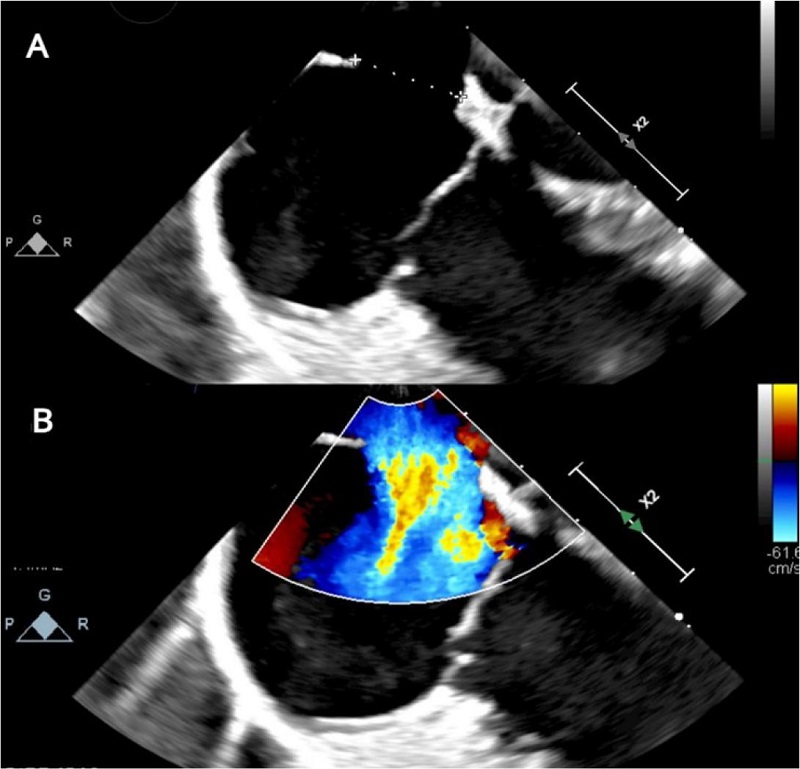

Presence of ostium secundum ASD of 14 mm with left to right shunt (Figure 2). Normal biventricular ejection fraction, enlargement of right cardiac chambers and left atrium, and noticeable MV insufficiency (Figures 3C, 4A, 4B).